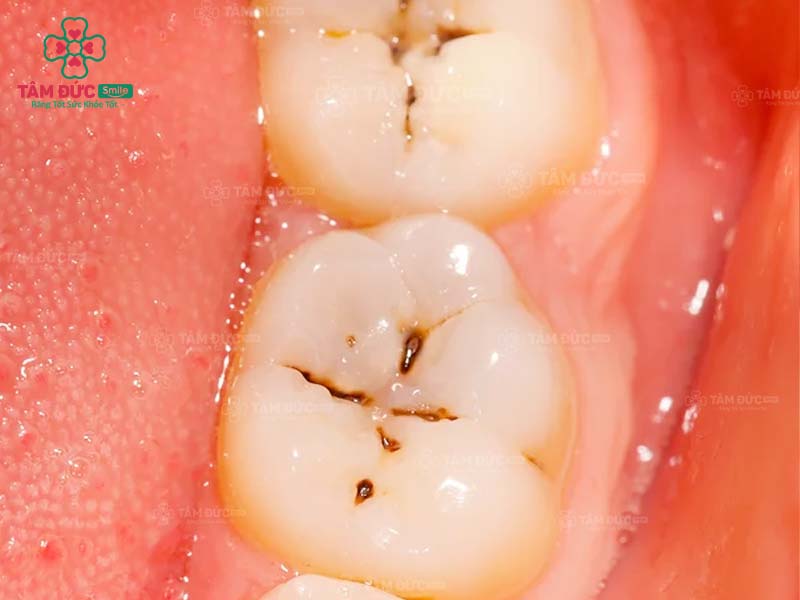

1.1. Răng bị sâu

Khi răng bị sâu, trên thân răng xuất hiện các lỗ nhỏ li ti. Đây chính là vị trí trú ngụ của hàng nghìn loại vi khuẩn. Cùng với thói quen chăm sóc răng miệng không tốt, ăn thực phẩm chứa nhiều đường, lỗ sâu răng sẽ lớn dần và gây đau nghiêm trọng. Nguy hiểm nhất chính là nhiễm trùng và mất răng vĩnh viễn.

Trám răng giúp lấp đầy các lỗ hổng trên thân răng. Nhờ đó, các triệu chứng khó chịu, biến chứng do răng sâu được loại bỏ triệt để. Thẩm mỹ của chiếc răng bị sâu nói riêng và cả hàm răng nói chung đều được phục hồi.

răng sâu cần trám răng

răng hàm bị sâu

răng nanh bị sâu cần trám